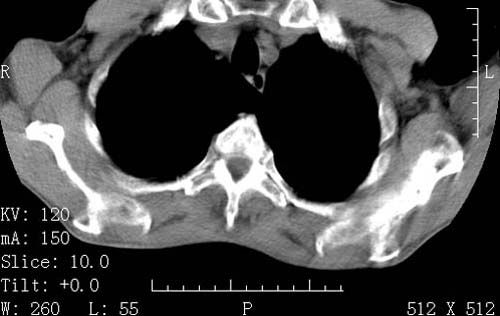

标题: CT16691:m 67 胃镜确诊食管下段及贲门癌 [打印本页]

标题: CT16691:m 67 胃镜确诊食管下段及贲门癌

术前查体,双肺部结节是转移?结核?请点评

1)符合食管癌表现。2)两肺及纵隔淋巴结多发性转移瘤。3)左肺上叶舌段及两肺下叶炎症感染。

食管癌伴双肺转移,评述:肺部毛细血管网丰富,全身血液均快速流经肺部,癌细胞容易过滤定植,形成转移瘤,影象特点为以毛细血管末梢为中心的结节灶,边缘光滑锐利,少见有中心空洞着,不同来源的转移瘤可有各自特点,如甲状腺癌为双肺弥漫性微结节,本例有原发灶,双肺影象灶典型,左肺舌段条带状网格样伴胸膜天幕征,可视为癌性淋巴管炎。